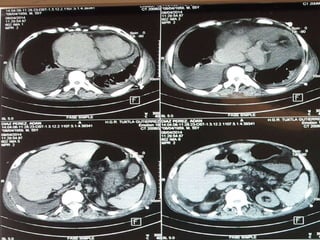

Cardiovascular

Cardiopatía esta presente en el

50-80% de los pacientes.

La cardiopatía típica es la estenosis

valvular pulmonar con displasia

valvular (20-50% de los casos).

La miocardiopatía hipertrófica esta